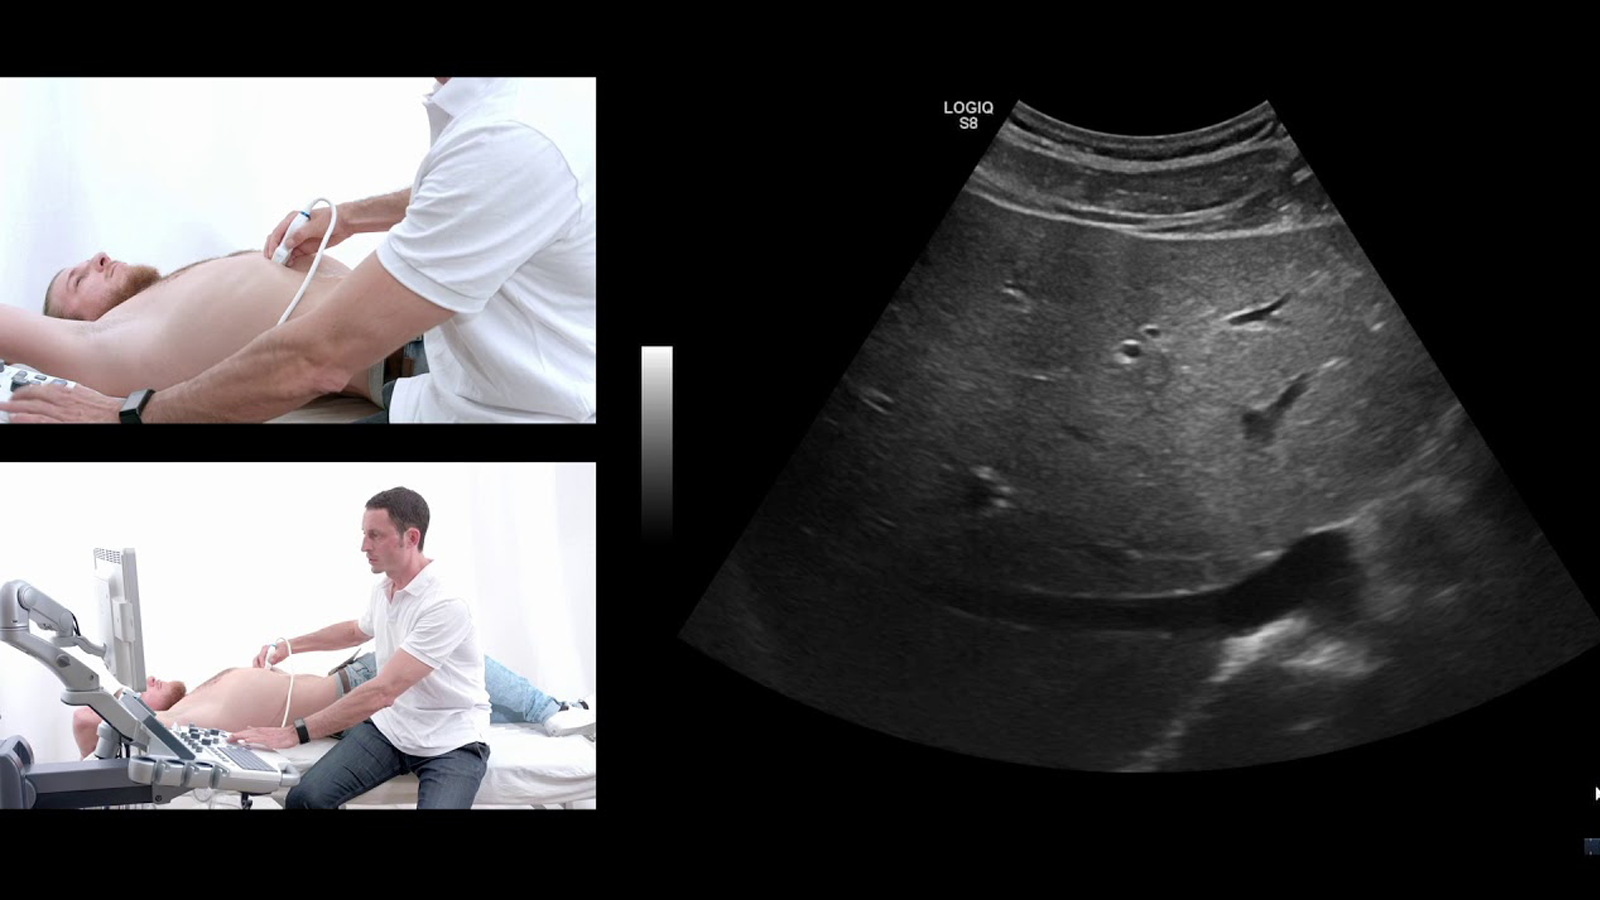

Ultrasound

The liver Foundation provides the facility of ultrasound of the patients with hepatitis B and C to check whether the liver is inflamed or not. Ultrasound is a painless test in which high frequency sound waves are used to produce inner structural images of patient’s body. Our doctors places a handheld probe called a transducer against patient’s abdomen, and the transducer sends an image of the liver to a computer monitor, where it is analyzed for further treatment.